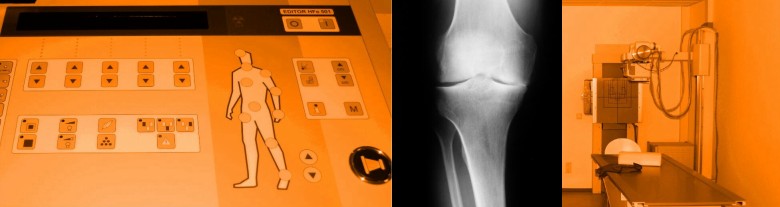

Radiologische Untersuchungen:

Zur Diagnostik des gesamten Skelettsytems, Untersuchung bei Verdacht auf Knochenbrüche, Sportverletzungen, Gelenkschäden, degenerativen Veränderungen und Tumorerkrankungen. Mit unserer hochmodernen Röntgenanlage mit digitaler Bildauswertung können wir Ihnen aussagekräftige Bildgebung mit der geringstmöglichen Strahlenbelastung garantieren. Dies ist z.B. bei der Behandlung von Kindern von großer Bedeutung.

Das Ergebnis der Untersuchung kann als Bildausdruck oder auf digitalem Speichermedium mitgegeben werden.